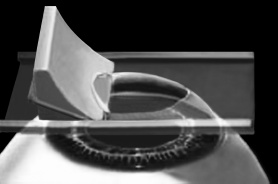

ЛАСИК – основной метод лазерной коррекции в мире в настоящее время. По большому счету, ФРК и ЛАСИК – единственные методы коррекции. Остальные методы являются либо модификациями ФРК и ЛАСИК, либо «компромиссом» между ними. Эпителий роговицы не трогают, так как он – залог быстрого заживления. Накладывают на глаз вакуумное кольцо – стальную присоску кольцевидной формы с присоединенной к нему трубочкой. Через трубочку из присоски отсасывается воздух, чтобы создать относительный вакуум. Отсасывает воздух главный аппарат для проведения ЛАСИКа – микрокератом. Это прибор размером с коробку из-под обуви. Его предназначение – срезание поверхностной крышки роговицы. К глазу присоединяют вакуумное кольцо, окружающее роговицу. Глаз четко фиксируется относительно кольца и сдвинуться с места может только с кольцом, в отверстие которого выступает купол роговицы. Затем к кольцу присоединяется головка микрокератома. Это второй инструмент микрокератома и соединяется с ним или шнуром, или тонким шлангом. Головка крепится на турбине, и вместе они имеют вид толстой шариковой ручки с обрубленным концом. Эту «ручку» хирург держит в правой руке, а вакуумное кольцо – в левой. Эта «ручка» нужна, чтобы сформировать крышечку роговицы. Внутри головки есть очень острое одноразовое лезвие. Турбина, соединенная с головкой, может двигать одноразовое лезвие туда-сюда, пилящими движениями. Можно резать роговицу, как хлеб, – пилящими движениями. И тут самое главное – скорость. Одноразовое лезвие делает 15000 пилящих движений в минуту. При такой скорости назвать это срезанием роговицы уже трудно, скорее это отслаивание верхних слоев. ![]() Рис. 3. Схема формирования роговичного лоскута с помощью микрокератома. Иллюстрация с сайта Международного лазерного центра www.optics.ru Итак, головка присоединяется к вакуумному кольцу и по специальным полозьям двигается над куполом роговицы (рис. 3). Срез, или отслаивание (называйте, как хотите), проводится не полностью, у крышечки (роговичного лоскута) остается маленький участок на периферии, соединяющий ее с роговицей (рис. 4). ![]() Рис. 4. Роговичный лоскут сформирован. Иллюстрация с сайта Международного лазерного центра www.optics.ru После формирования роговичного лоскута убирают инструменты микрокератома, затем шпателем откидывают его вбок (рис. 5). Обнажается роговичное ложе, то есть место, на котором лежал лоскут. Это верхние слои стромы роговицы. Ложе осушают тупфером и так же, как и при ФРК, настраивают лазер и испаряют несколько микрон вещества стромы (рис. 6). Потом промывают строму водой и шпателем укладывают лоскут на место. ![]() Рис. 5. Роговичный лоскут откинут в сторону. Иллюстрация с сайта Международного лазерного центра www.optics.ru ![]() Рис. 6. Луч эксимерного лазера испаряет на роговичном ложе несколько микрон стромы роговицы. Иллюстрация с сайта Международного лазерного центра www.optics.ru Стоит один раз моргнуть и лоскут скомкается и зрения не будет. Его бы пришить на место. Но швы деформируют роговицу. Все проще. Лоскут разглаживают мокрым тупфером, прижимая его ровненько к старому месту (рис. 7 и 8). Только место не старое, с роговичного ложа удалили несколько микрон в виде причудливой ямки (при коррекции близорукости). ![]() Рис. 7. При коррекции близорукости на роговичном ложе формируется «ямка». Иллюстрация с сайта Международного лазерного центра www.optics.ru ![]() Рис. 8. Роговичный лоскут укладывается на место. Иллюстрация с сайта Международного лазерного центра www.optics.ru Края роговичного лоскута осушают сухим тупфером. Влага, оставшаяся под лоскутом в ямке роговичного ложа, высасывается в тупфер. Лоскут притягивает к ложу, как вакуумную присоску. Вакуумом начали, вакуумом закончили. Ждем, когда закончится приживление лоскута к ложу. Эпителий цел и невредим. А значит, никаких болей. Около трех часов возможны слезотечение и светобоязнь. И все (рис. 9). ![]() Рис. 9. Форма роговицы до проведения коррекции (а) и после коррекции близорукости (б). Испарение нескольких микрон толщины роговицы привело к уменьшению ее кривизны в центре. Иллюстрация с сайта Международного лазерного центра www.optics.ru Хирурги о ЛАСИКе говорят: «90 % хирургии и 10 % долечивания». Лазерный субэпителиальный кератомилез (LASEK) Модификация ФРК. Чтобы укоротить неприятный послеоперационный период, эпителий, обработанный спиртовым или солевым раствором, отслаивают очень бережно, с помощью специальных инструментов, в виде цельного лоскута. А после испарения эксимерным лазером боуменовой мембраны и нужного количества слоев стромы этот эпителиальный лоскут укладывают обратно и, чтобы он не сместился, прижимают мягкой контактной линзой. Через 3–4 дня эпителий заживает, а благодаря линзе и даже еще не приживленному эпителиальному лоскуту боль и светобоязнь не беспокоят пациента с первых часов после коррекции, а зрение восстанавливается на пару недель быстрее, чем при ФРК. Также одной из модификаций ФРК является MAGEK. Основным отличием от ФРК является применение препарата Митомицин С (Mitomycin-С), который блокирует «слишком быстрое деление клеток» и снижает риск возникновения хейза. Эпи-ЛАСИК (Epi-LASIK) Нечто среднее между ЛАСИК и LASEK. Для отделения эпителия используются не спиртовой или солевой растворы, а специальный аппарат, очень похожий на микрокератом. Аппарат называется эпикератомом. Он отслаивает эпителий вместе с частью боуменовой мембраны в виде лоскута, похожего на лоскут при ЛАСИКе, только гораздо тоньше. После проведения коррекции лоскут также прижимают контактной линзой. Но не поврежденный химическим ожогом эпителиальный лоскут, да еще с остатками боуменовой мембраны, значительно сокращает период заживления и восстановления и снижает другие недостатки ФРК и LASEK, о которых будет сказано ниже. Рефракционный эксимерлазерный интростромальный кератомилез (РЭИК) |